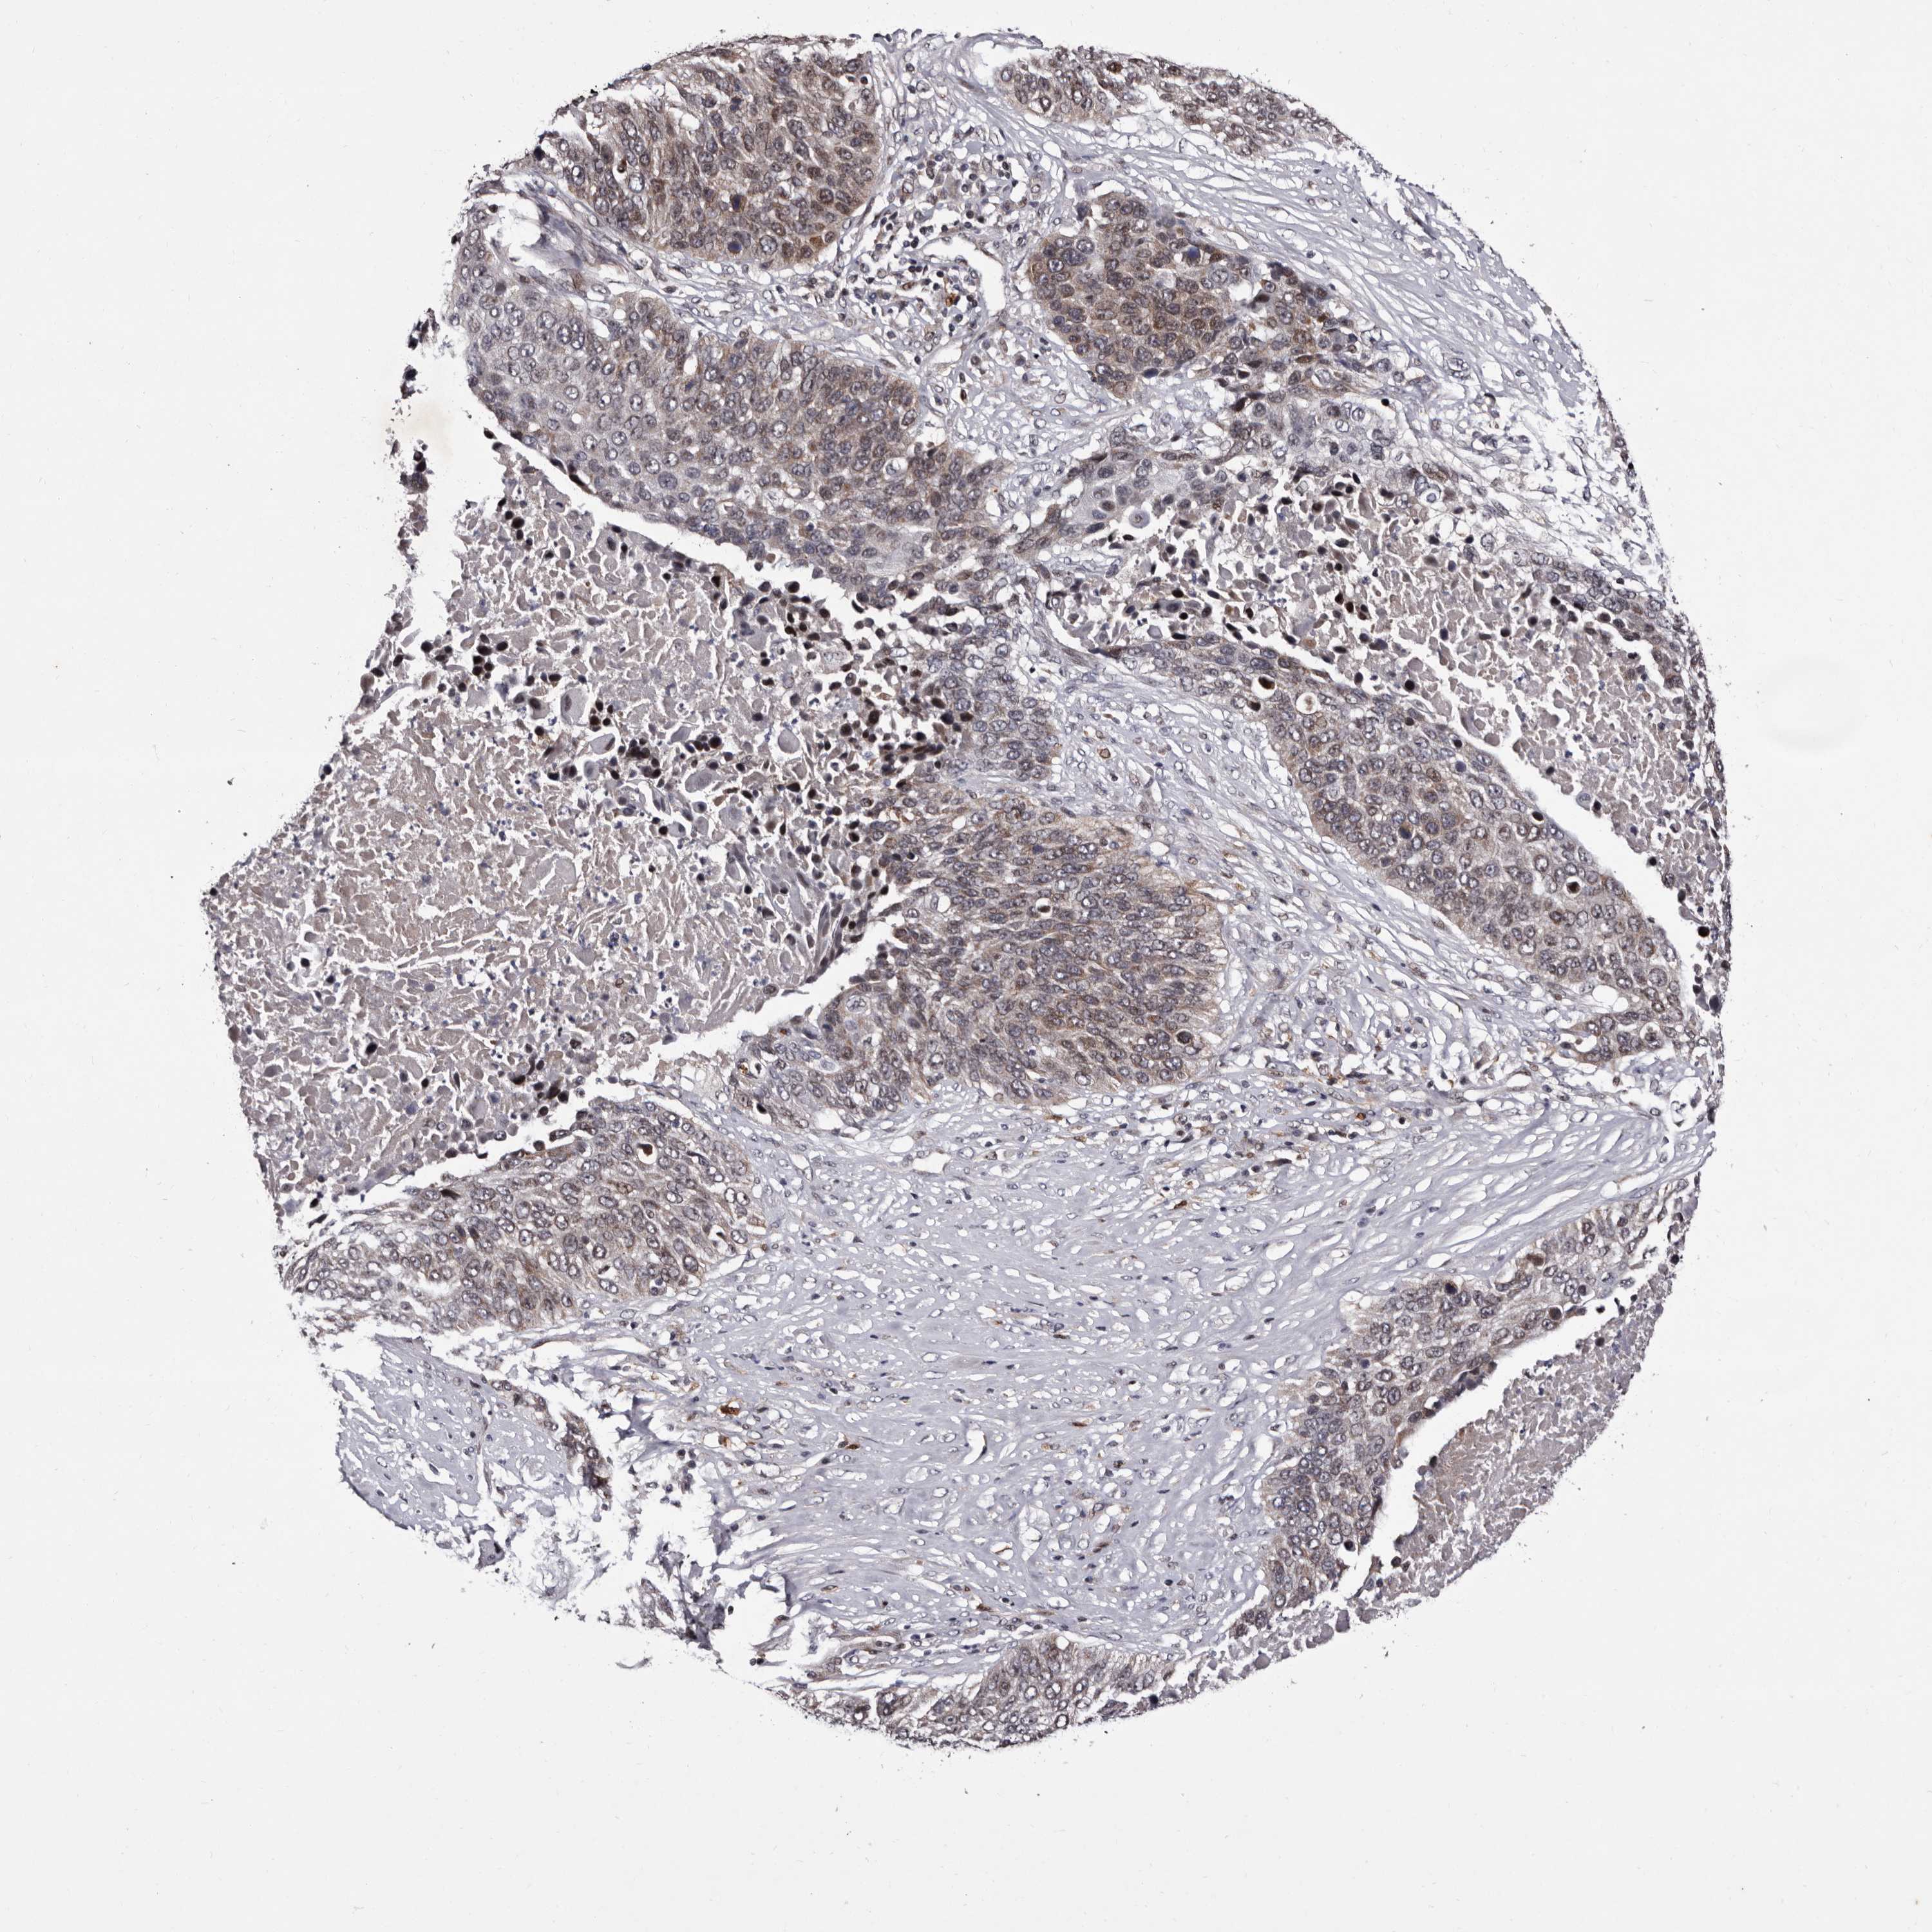

CANCER LUNG CANCER Show tissue menu

LUAD TCGA LUAD VALIDATION LUSC TCGA LUSC VALIDATION PROTEIN LUAD CPTAC PROTEIN LUSC CPTAC PROTEIN EXPRESSION